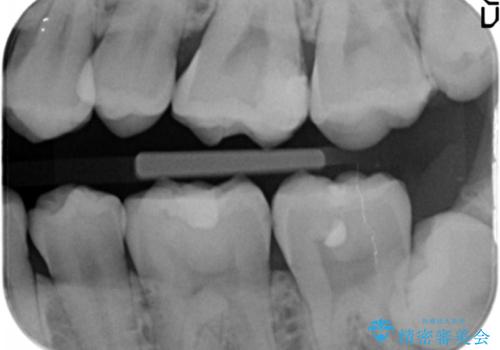

- 奥歯にフロスを通すとにおいがすることを気にされ、来院された患者様です。

精査したところ、奥歯に充填された保険内のコンポジットレジンの適合が悪いことにより、汚れがたまりやすい状態でした。

不適合なレジンを除去し、セラミックインレーによる治療を行いました。(右上76左上67右下7の計5本)